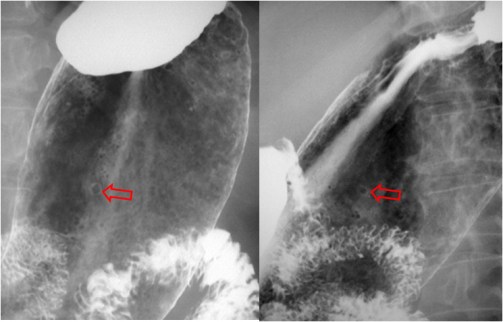

SIGNO DEL HÍGADO AUSENTE

La identificación de aire intestinal en el hemitórax derecho (en la placa de tórax de un neonato) –flecha- permite realizar el diagnóstico de hernia diafragmática congénita. En aquellos casos en los que únicamente se produce la herniación del hígado, el diagnóstico suele ser erróneo. La combinación de la opacificación del hemitórax junto a la presencia de aire intestinal en el cuadrante superior derecho (Signo del hígado ausente), debe sugerir el diagnóstico de hernia hepática intratorácica.